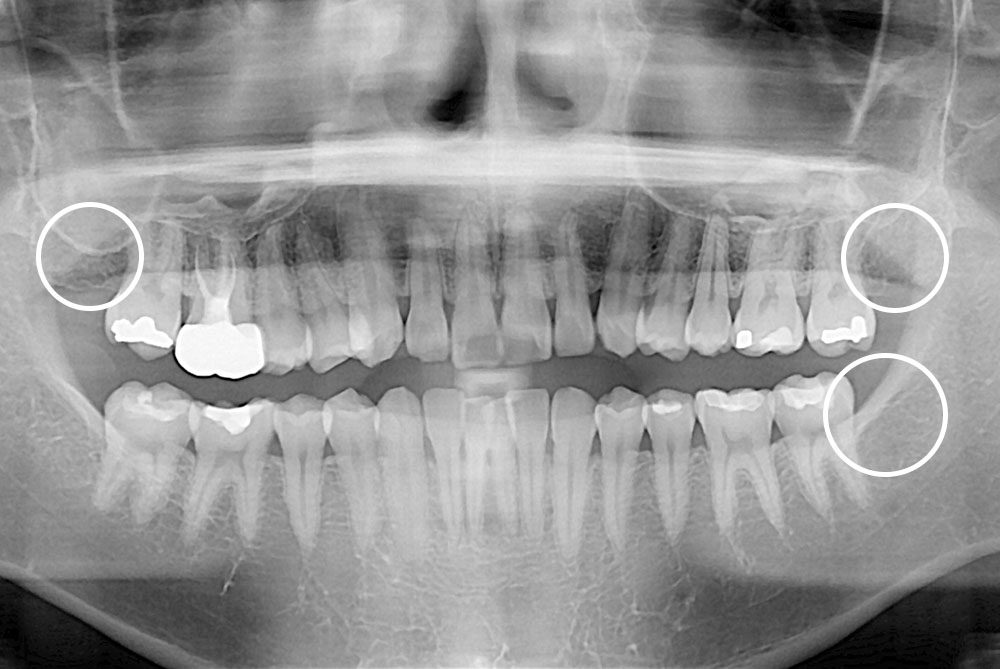

[사랑니] 매복 사랑니 발치

치료전 : 2017-11-28